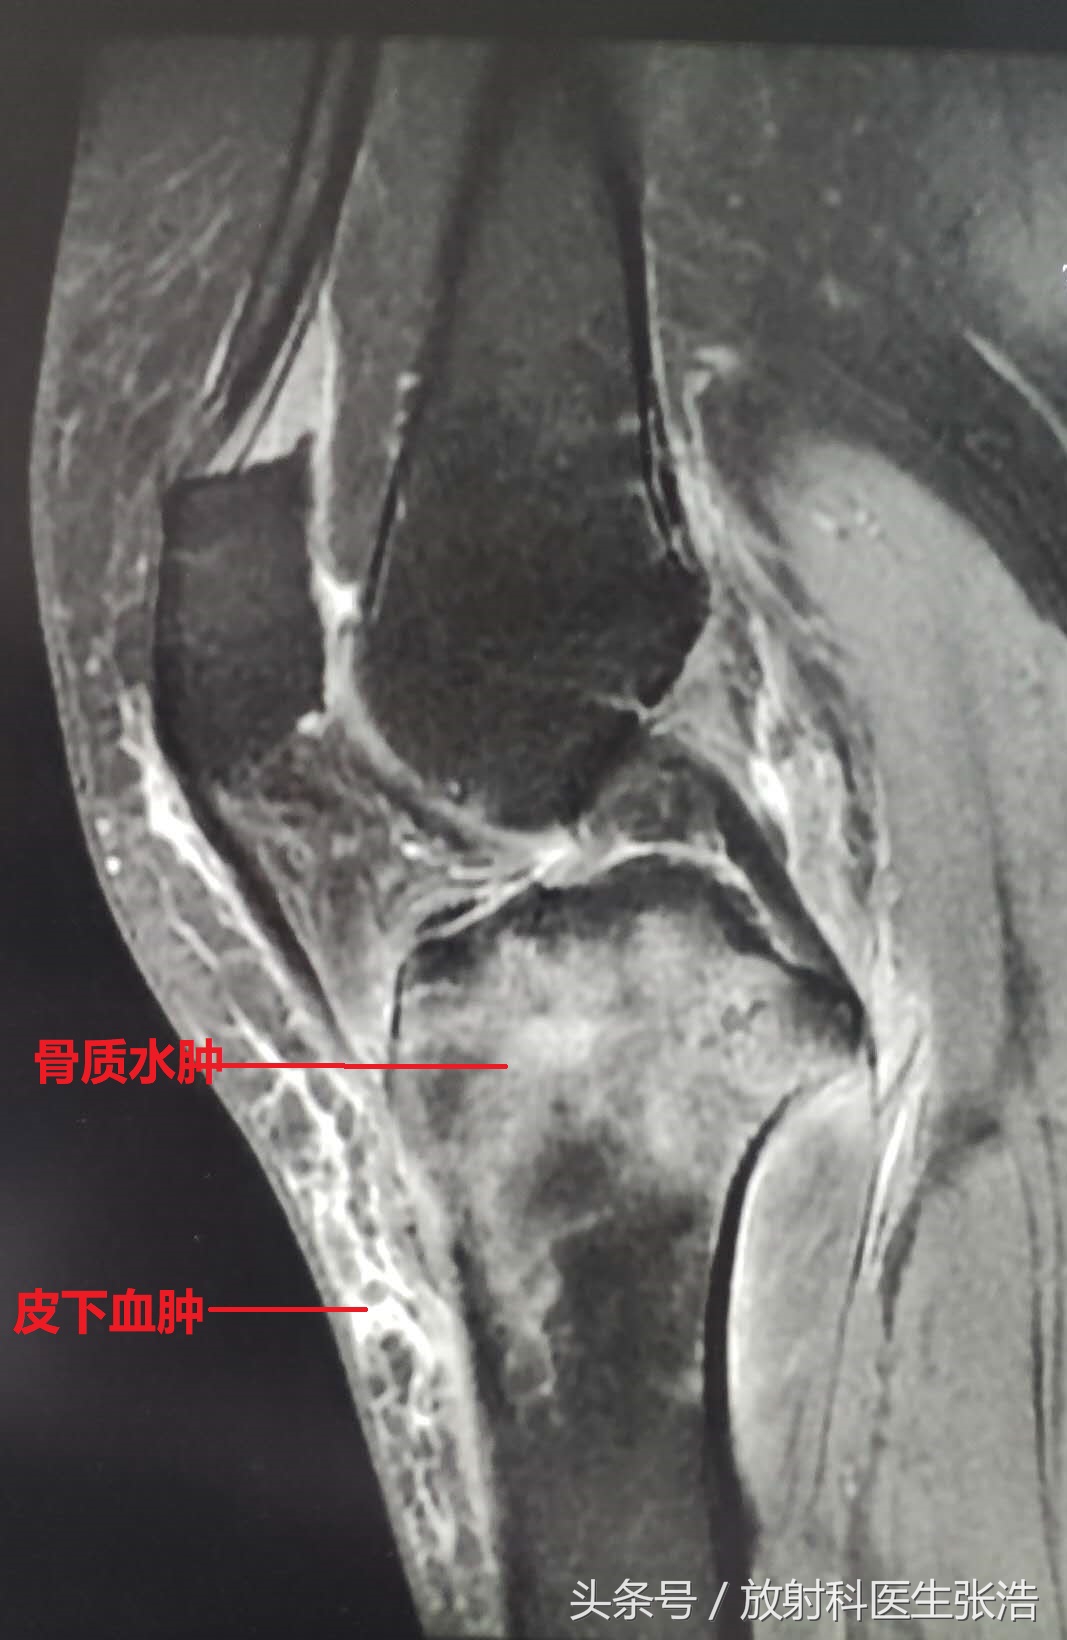

拍了x光片骨头没有问题,但是膝关节任然疼难忍!问题就在软组织结构了!这个时候我们就需要做膝关节的核磁共振检查,这不做不知道,做了结果很多时候真的能吓自己一大跳!我们一起来看看几个膝关节疼痛的患者做完核磁共振的图像结果!

1、第一张可以看到其胫骨上段大片混杂长T2信号,说明胫骨虽然没有骨折,但是里面骨小梁已经出现了细微的损伤水肿;再看胫骨前面的软组织内,肌肉间隙也是很多水样的信号,那是外伤造成皮下血肿信号!x光片上是看不到的。